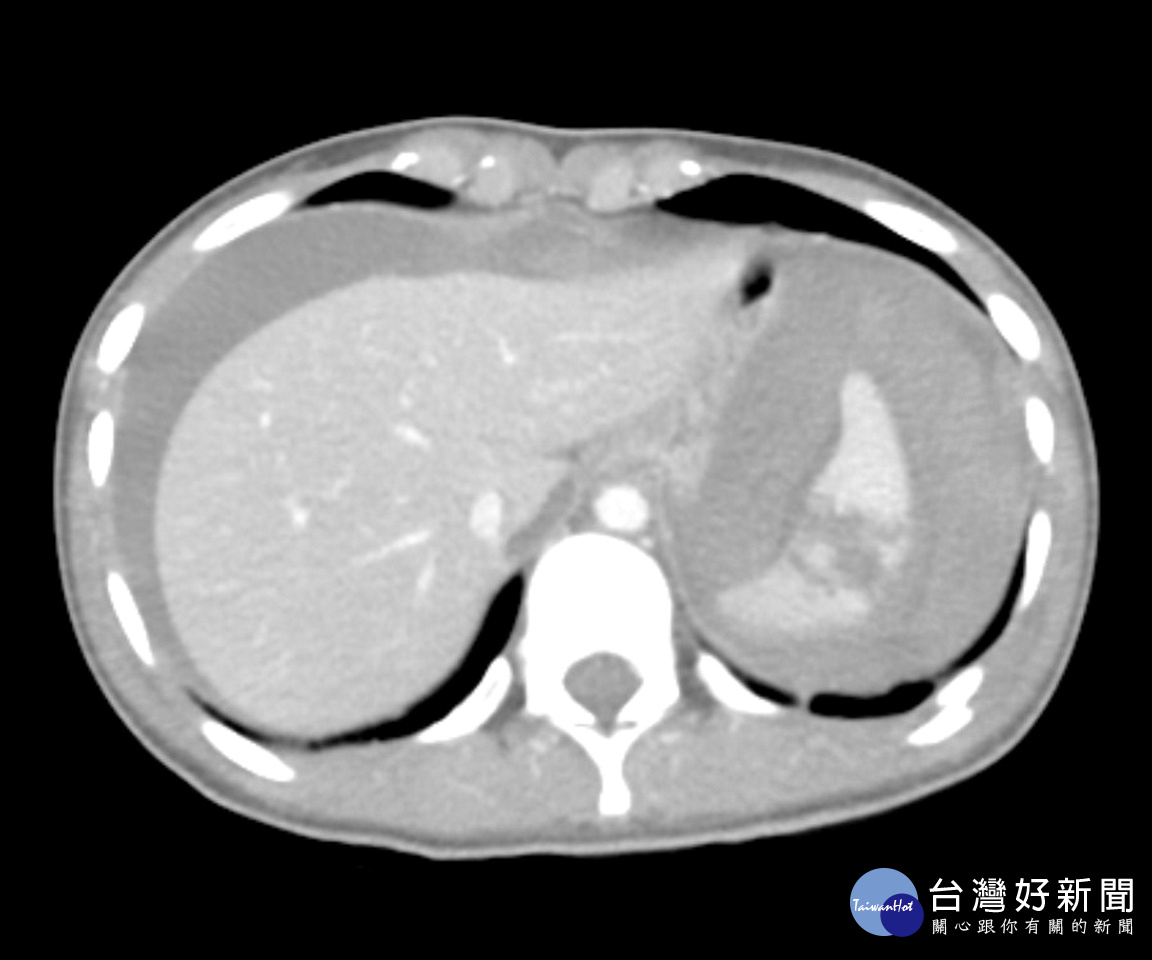

一位20歲就讀護理學系的吳姓女大生,日前於南投縣集集鎮上不幸發生車禍意外,緊急被送往鄰近的竹山秀傳醫院進行救治,急診醫師發現女大生臉色漸趨蒼白且有休克徵象,經超音波檢查與電腦斷層掃描診斷為脾臟破裂合併大量腹內出血(附圖),院方立即啟動重大外傷病人救護機制並安排緊急手術進行止血,術後女大生生命徵象漸趨穩定轉至加護病房接受後續治療,近日已康復出院休養。

外科部主治醫師蘇啟成表示,脾臟破裂出血是一種嚴重的外傷急症,出血速度極快,病人常會迅速休克甚至死亡,女大生體重僅約40公斤,術中發現內出血已逾3000毫升,幾乎是瀕死狀態,開刀是在與時間賽跑,所幸最後終於成功搶回一條年輕生命。蘇醫師也呼籲民眾在車禍當下切莫自行評估身體狀況,宜盡速就醫以避免延誤搶救時機。